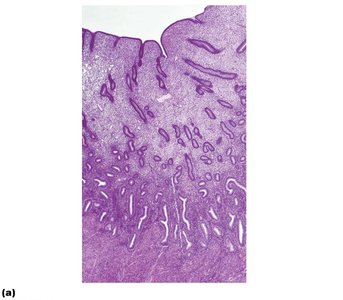

The endometrium consists of the stratum functionalis (shed during menstruation) and stratum basalis (regenerates new functionalis). The uterine arteries branch into arcuate and radial arteries, with spiral arteries supplying the functionalis and straight arteries supplying the basalis.

Histology of endometrium and its blood supply Diagram of uterine vascular supply